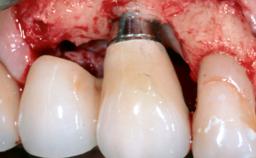

Treatment of Advanced Peri-Implantitis by Implant Removal Followed by Bone Reconstruction and New Implant Placement

Paolo Casentini and Matteo Chiapasco present a case in which the peri-implant defect was not suitable for a fully regenerative approach. It involves implant removal, use of a CAD/CAM customized titanium mesh in the grafting phase, and placement of new implants. A 62-year-old woman was referred for consultation regarding her implant-supported prosthesis replacing teeth 14 to 16. The patient’s main concern was pain and recurrent swelling in the right posterior maxilla. The patient also reported difficulty and discomfort when brushing the area. The patient reported she had been treated in another country, where she had received three implants in combination with sinus-floor augmentation for the replacement of the posterior maxillary teeth three years earlier. The patient indicated “endodontic complications” to be the reason for the extraction of the teeth.